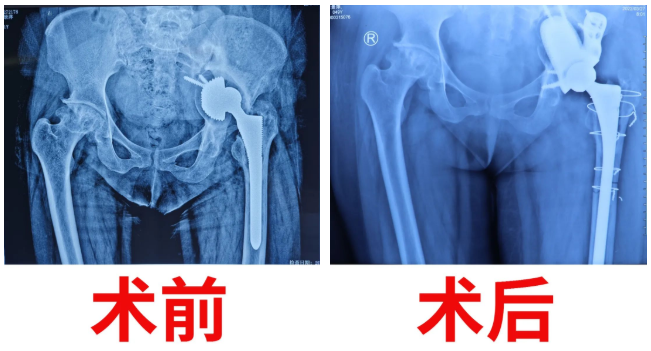

在骨科醫(yī)護(hù)團(tuán)隊(duì)的悉心照顧和鼓勵(lì)下,術(shù)后復(fù)查顯示假體植入非常理想,患者髖臼骨缺損填補(bǔ)滿意、關(guān)節(jié)假體復(fù)位滿意,同時(shí)也成功地消除了肢體不等長的這個(gè)差距,疼痛感完全消失,髖關(guān)節(jié)各個(gè)方向被動(dòng)活動(dòng)基本達(dá)到要求?;颊呤中g(shù)當(dāng)天就坐起了身,術(shù)后第10日即可下床扶柺慢行。